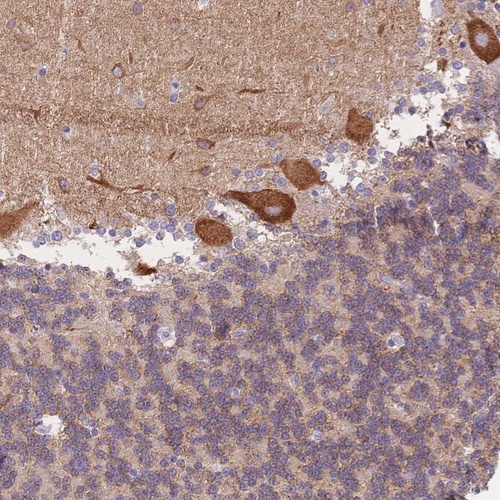

Immunohistochemical staining of human cerebellum shows strong cytoplasmic positivity in Purkinje cells.